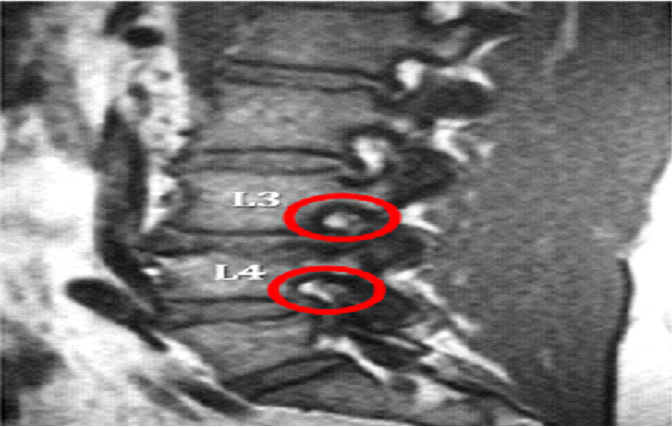

Different factors can lead to foraminal stenosis, including degenerative disc disease, osteoarthritis and herniated discs. When changes take place due to aging and wear, the symptoms of foraminal stenosis can occur. Bone spurs can also enter the spinal canal, narrowing the space at the nerve roots.